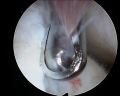

Les progrès techniques de la chirurgie mini-invasive du poignet ont permis de réaliser l'ablation de ces kystes sous arthroscopie, c'est-à-dire au moyen de deux mini incisions permettant, l'une d'introduire une caméra de 1,9 à 2,7 mm de diamètre et l'autre des instruments mécaniques et de radiofréquence de 2-3 mm de diamètre (figure 2). La base d'implantation du kyste est repérée (une IRM ou une échographie préalable ont guidé le choix des petits incisions-figure 3) et retirée. Le liquide mucoïde s'écoule alors dans l'articulation et est aspiré alors que la paroi du kyste est excisée par la profondeur sans nécessité d'incision supplémentaire (figure 4). On visualise ainsi les tendons extenseurs des doigts et du poignet qui doivent être contrôlés et protégés durant toute l'intervention (figure 5), constituant le seul risque spécifique de cette arthroscopie. l'intérêt de cette technique n'est pas qu'esthétique, bien que l'indication du geste opératoire soit essentiellement cosmétique (figure 6) mais surtout plus logique et efficace que la chirurgie dite classique, car il permet le repérage et l'excision du point de départ de cette "tumeur" bénigne, diminuant ainsi le risque théorique de récidive. On peut ainsi diagnostiquer et retirer des petits kystes du ligament scapho-lunaire (figure 7), il y a encore peu surnommés "occult ganglions" car peu accessibles aux autres procédés d'exploration du poignet, ils peuvent être douloureux notamment lors des appuis en flexion dorsale.